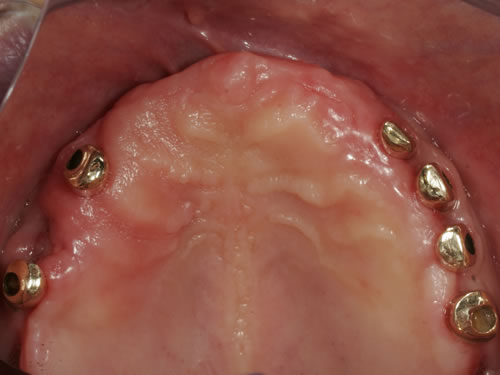

Abb. 3.8: Individuelle Stegversorgung aus Gold auf vier Implantaten im zahnlosen Unterkiefer.

Abb. 3.9: Prothesenansicht von unten mit grazil eingearbeiteten Halteelementen.

Abb. 3.10: Zahnloser Oberkiefer mit 6 Galvano-Teleskopen.

Abb. 3.11: Prothesenansicht von unten mit grazil eingearbeiteten Halteelementen.

Für den zahnlosen Ober- und Unterkiefer werden dies häufiger Stegkonstruktionen oder Teleskopversorgungen sein (Abb. 8.8 bis 8.16).

Abb. 8.8: Individueller Steg auf 4 Implantaten im zahnlosen Unterkiefer.

Abb. 8.9: Eingesetzter prothesenartiger Zahnersatz.

Abb. 8.10: Individueller Stahlsteg auf 4 Implantaten im zahnlosen Oberkiefer.

Abb. 8.11: Eingegliederter graziler, herausnehmbarer, gaumenfreien Zahnersatz.

Abb. 8.12: Zahnloser Oberkiefer mit 8 Implantaten und eingesetzter Unterkonstruktionen.

Abb. 8.13: Abnehmbare, grazile Brücke.

Abb. 8.14: Zahnloser Oberkiefer mit vier Teleskopen.

Abb. 8.15: Ansicht des Zahnersatzes von unten.

Abb. 8.16: Eingegliederter gaumenfreier Zahnersatz.